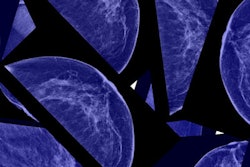

Dense breast tissue is a risk factor for breast cancer due to the masking effect it can have on mammography. Over the last decade, efforts have been made to establish notification practices to make women aware of their own tissue density on mammography screening, and, if appropriate, to encourage additional screening.

The researchers compared agreement between the women's self-reported breast density and their BI-RADS score within the previous five years and assessed women's knowledge of the implications of having dense breast tissue and their feelings about breast cancer screening.